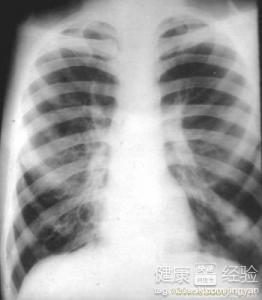

支氣管炎是一種常見的呼吸系統(tǒng)疾病,其癥狀包括咳嗽、咳痰、呼吸急促等,許多患者關心的問題是:支氣管炎能自愈嗎?本文將詳細解析支氣管炎的類型、癥狀、治療方法以及能否自愈的問題,幫助患者更好地了解并應對這一疾病。

支氣管炎是指氣管、支氣管黏膜及其周圍組織的炎癥,根據(jù)其發(fā)病的急緩,可分為急性支氣管炎和慢性支氣管炎,急性支氣管炎通常由于病毒、細菌等感染引起,癥狀明顯且病程較短;而慢性支氣管炎則由于長期吸煙、空氣污染等因素導致,癥狀持續(xù)較長時間,易反復發(fā)作。

支氣管炎的典型癥狀包括咳嗽、咳痰、呼吸急促等,部分患者可能伴有發(fā)熱、胸悶等癥狀,咳嗽通常為首發(fā)癥狀,隨著病情的發(fā)展,逐漸出現(xiàn)咳痰,痰量可能因病情嚴重程度而異,在嚴重的情況下,患者可能出現(xiàn)呼吸困難、喘息等癥狀。